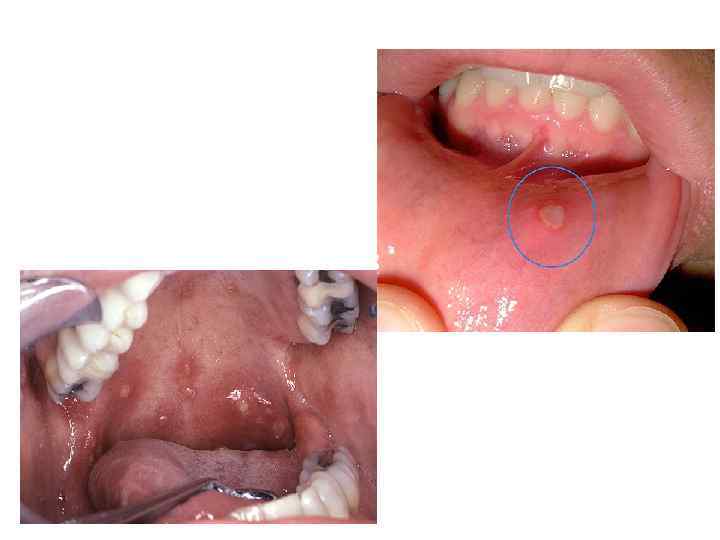

• Герпетический стоматит – острое или рецидивирующее воспаление слизистой оболочки полости рта, проявляющееся быстроразвивающимися везикулярными элементами (пузырьками), сопровождающее общую герпетическую инфекцию организма. Особенностью герпетической инфекции является пожизненное носительство вируса после перенесенного заболевания

Герпетический стоматит • Причиной заболевания являются: Вирус простого герпеса 1 типа (ВПГ I) или Вирус простого герпеса 2 типа (ВПГ II), которые проявляют тропизм к ганглиям тройничного нерва и спинномозговым ганглиям области крестцово подвздошного сочленения соответственно. • Клинически в полости рта герпетическая инфекция проявляется в 2 формах: • Острый герпетический стоматит; • Хронический рецидивирующий герпес.

Острый герпетический стоматит • Стоматитом чаще болеют дети от одного до трех лет, а так же подростки и молодежь. • Инкубационный период заболевания продолжается 1 4 суток. • Сначала появляются жалобы на плохое самочувствие с повышением температуры тела от 37 до 37, 5°С. При этом некоторые шейные и челюстные лимфоузлы увеличиваются. • Во рту — отечность и покраснение десен, а так же появление пузырьков, заполненных прозрачной жидкостью. Пузырьки быстро «лопаются» и появляются эрозии. Афты формируются 4 5 дней. • В это время больной жалуется на дискомфорт, жжение и зуд во время пережевывания пищи. Лечение нужно начинать вовремя, чтобы состояние заболевшего не ухудшилось. При правильном лечении на восьмой десятый день больной выздоравливает.

Хронический рецидивирующий герпес • Острый стоматит может перейти в хроническую форму рецидивирующего герпеса. При этом время от времени появляются одиночные или множественные высыпания на губах, во рту – на небе, на слизистой глаз, половых органов и крыльев носа. • Появление герпетических высыпаний сопровождается чувством жжения, а в дальнейшем эта пузырчатая сыпь образует слившиеся эрозии. • Во время приема пищи у больного появляется дискомфорт и боли во рту.